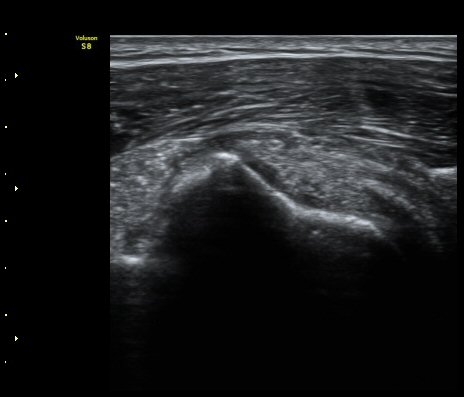

ÃÊÀ½ÆÄ °Ë»ç

À̵ιڱ٠Ⱦ´Ü¸é°Ë»ç¿¡¼­ Á¡¾×³¶³» °í¿¡ÄÚ ¼®È¸È­ À½¿µµéÀÌ °üÂûµÊ(±×¸² 1, 2, 5)

À̵ιڱ٠Á¾´Ü¸é°Ë»ç¿¡¼­µµ Á¡¾×³¶³» ¼®È­È­ À½¿µÀÌ °üÂûµÊ(±×¸² 4).